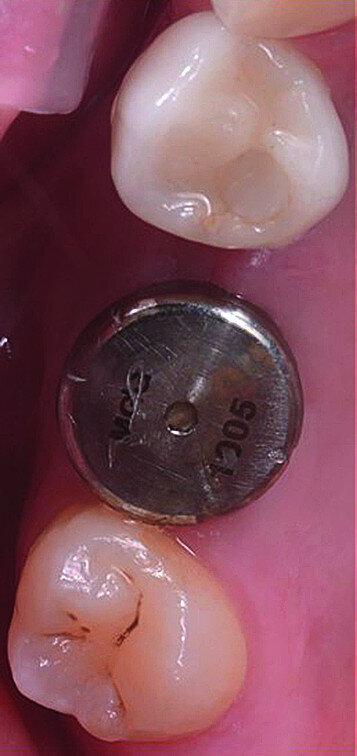

Once the implant bed had been prepared, a 7 × 10 mm implant (AnyRidge) was placed. After placement, the ISQ (Implant Stability Quotient) was measured with a stability meter (Mega ISQ, MegaGen), and the value was 72. According to the ISQ scale, this represents high stability (Fig. 6b). A 10 × 7 mm healing screw (AnyRidge) was placed, along with a plug of A-PRF (advanced platelet-rich fibrin; PRF process by Choukroun) in order to accelerate the healing process, and sutured with 4/0 polypropylene (Hu-Friedy; Figs. 7–10). After the surgical procedure, the White Clinic postoperative protocol was applied: application for eight minutes of the ATP38 laser (Swiss Bio Inov), based on the principle of Low Level Laser Therapy that acts on the cellular metabolism and provides a better and faster postoperative healing. The patient was instructed to use a 0.2% hyaluronic acid gel (Gengigel, Ricerfarma) and 0.1% hyaluronic acid mouthwash (Gengigel First-aid, Ricerfarma) for one week after surgery, with the goal of accelerating the healing process. One week after surgery, the sutures were removed, ozone was used to disinfect the area around the implant, and the ATP38 was applied for eight minutes to promote healing.